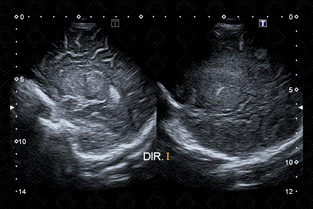

Descrição das figuras 4 e 5: Ultrassonografia transfontanela, planos parassagitais direito e esquerdo, varrendo até o nível da ínsula.

Descrição da figura 6: Ultrassonografia transfontanela, varredura com transdutor linear de alta frequência.